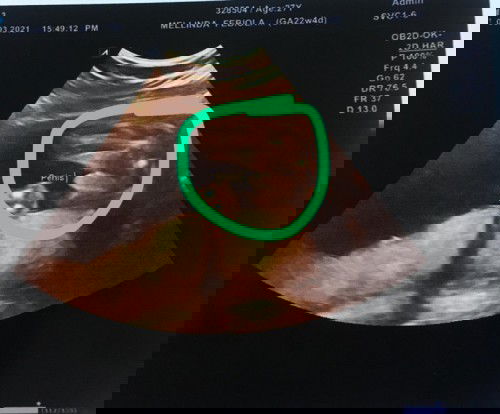

waktu pertama kali dikasih tau dokter kandungan hplnya 13 Juli 2021, setelah usia kandungan 4 bulanan maju jadi 6 Juli 2021 dokter pun mengatakan pake HPL yang ini saja kalau nanti ditanya-tanya lagi. karena rencana saya melahirkan di daerah ibu saya tinggal, saya masih meraba-raba dokter mana yang cocok untuk saya, alhasil saya gonta-ganti dokter kandungan... usia 5-6-7 bulan masih dengan hpl yang sama 6 Juli 2021 dan usia kandungan yang tak jau berbeda begitupun di aplikasi TAP tapi hari ini saya USG di rumah sakit karena niatan ingin melahirkan di rumah sakit tersebut, dokter mengatakan usia kandungan saya 36 minggu beda seminggu dengan aplikasi TAP anehnya saya lihat di print USG kandungan saya jadi 33 minggu, mundur jauh. saya sudah cek di buku pink dokter pun menulisnya 36 minggu, saya jadi galau bunda sebenernya usia kandungan saya 36 minggu atau 33 minggu sesuai print USG, apakah bisa usia kandungan jadi mundur seperti itu ? mohon pencerahannya bunda 🙏🏻#ingintahu #jangandibully #firstbaby #pleasehelp